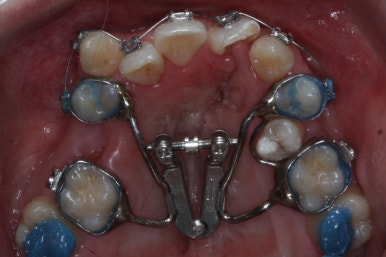

좁아져 있는 위턱뼈를 가로로 넓혀주기 위해서 악궁확장장치를 사용했습니다.

윗니는 선천결손으로 치아가 2개가 모자랐고 앞니도 거꾸로 물리는 상황이여서 아랫니도 균형있게 2개를 추가로 더 뽑았습니다.

악궁확장과 동반하여 부산구순구개열 키다리아저씨치과에서는 브라켓을 부착하여 가지런하게 하는 작업을 시작하였습니다.

악궁확장이 시작될 시점과 악궁확장을 다 진행했을 시점의 비교입니다.

확실히 좁아져 있던 가로 넓이가 넓어진 것을 볼 수 있습니다.

악궁확장장치는 바로 제거할 경우 다시 원상태로 폭이 좁아질 수 있으므로 3~6개월은 유지해야 합니다.

만약 치아교정 없이 악궁확장장치만 사용한다면 유지장치가 매우 중요하게 됩니다.